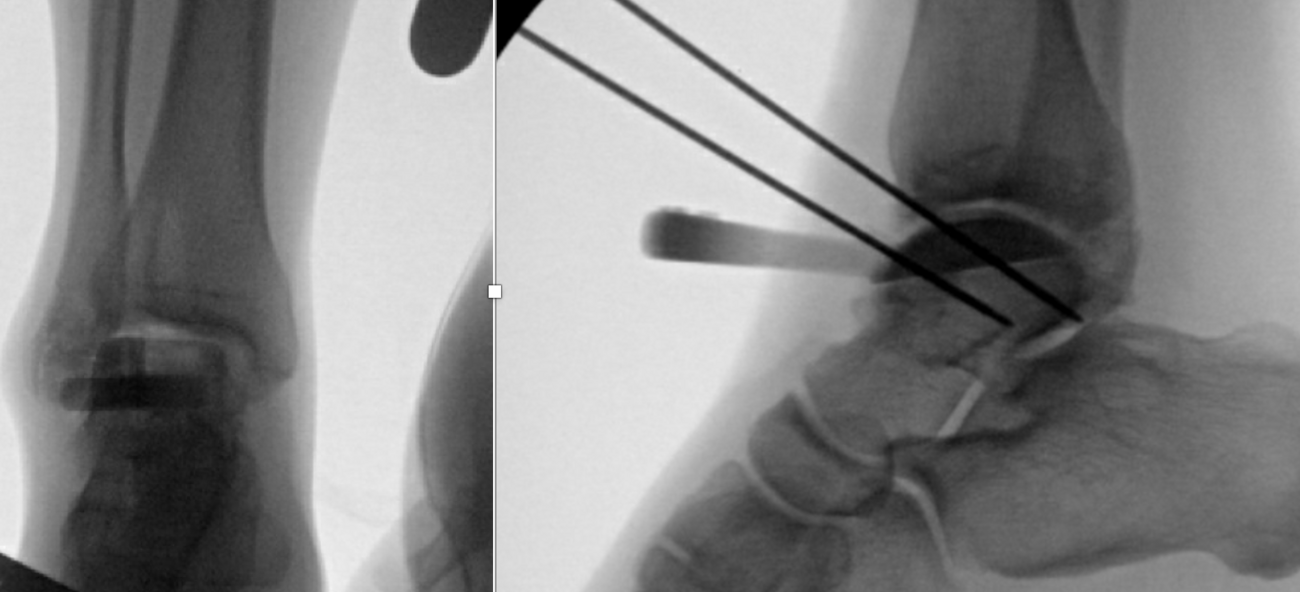

Her initial injury radiographs revealed a small lucent area of the talar dome consistent with an osteochondral defect. Radiographs three months later revealed a more distinct osteochondral defect with a detached fragment of the lateral dome. The MRI was consistent with the radiographs, showing the detached fragment, corresponding bone edema and lateral ligament injury.

New radiographs revealed a small lucent area of the lateral talar dome but no loose body or fragment. Treatment included non-steroidal anti-inflammatory drugs (NSAIDs) and bracing. A month later with no relief, we ordered a new MRI, which revealed an increased number of cystic changes to the lateral talar dome. There was no loose fragment and the cyst areas appeared contained, but it now involved a large area.

After a lengthy discussion, we ordered a computed tomography (CT) scan. Although she obtained relief from arthroscopy, it was short-lived. Other options discussed included autograft cartilage transfer and larger open bulk allograft replacement. The CT scan revealed a large portion of the lateral talar dome was involved. The cystic areas had grown in size and number to include much of the lateral shoulder. The lesion was uncontained and encompassed much of the anterior-posterior depth of the talus.